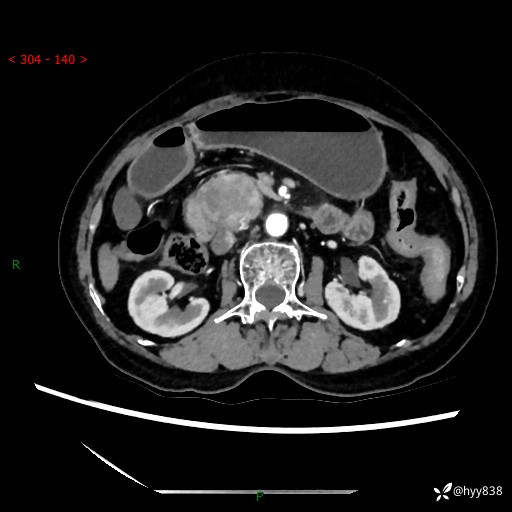

71岁/女,腹痛1月余。腹膜后肿物,间质瘤 VS 副节瘤 VS 平滑肌肉瘤---(有结果)

【患者信息】:71岁/女

【主诉】:腹痛1月余

【现病史及既往史】:患者于1月前无明显诱因出现右下腹部疼痛不适,呈阵发性隐痛,尚可耐受,放射至后背部及腰部疼痛,伴排便困难,不伴其它部位疼痛,无嗳气,无不洁饮食,无黑便,无恶心、呕吐、腹胀腹泻、呕血、发热、寒颤、厌油、黄疸,多次就诊于当地区太湖医院拍片示: 行抗炎等对症支持治疗,效果尚可。现患者上述不适症状明显进一步加重,为求进一步治疗遂来我院门诊就诊,门诊以“十二指肠肿瘤?”收住我科。 起病以来,精神、睡眠可,食欲可,大便异常、小便正常,体力、体重无明显下降。

【检查】:腹部CT增强扫描(外院CT平扫)